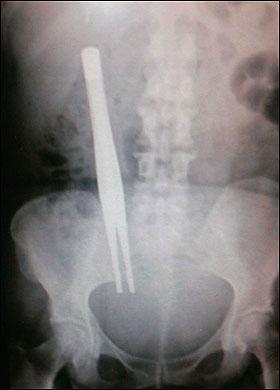

Şoke eden röntgen filmleri

Bu röntgen filmleri görenleri şaşkına çeviriyor!